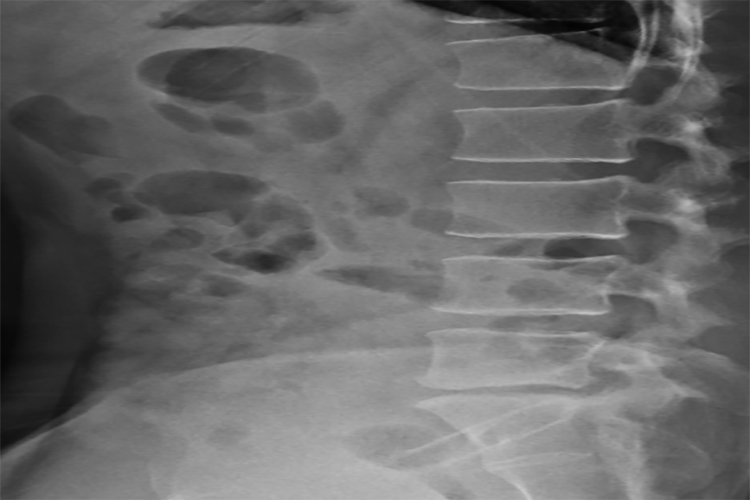

脊柱外观

腰椎间盘突出患者脊柱大多表现为腰椎生理前凸变浅,严重的患者生理前凸可完全消失,甚至出现腰后凸。部分的患者可以出现腰椎的侧凸,如果突出物在神经根的内侧,则凸向健侧。相反,如果突出物在神经根的外侧,则凸向患侧。在腰椎间盘突出时,腹部各方向活动度都会不同程度地受影响,其中以前屈受限最明显。

根据病史、症状、体征以及在X线平片上相应的节段有椎间盘退行性改变者,即可做出初步诊断,结合X线、CT、MRI等方法,能准确做出病变间隙、突出方向、突出物大小、神经受压情况的诊断。